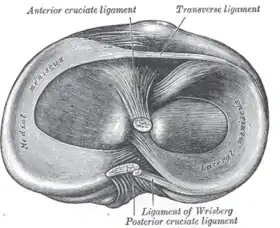

The medial collateral ligament, posterior cruciate ligament, anterior cruciate ligament, and lateral collateral ligament are the four primary ligaments of the knee. The medial and lateral collateral ligaments primarily provide support to varus and valgus forces whereas the anterior and posterior cruciate ligaments prevent anterior and posterior translation of the tibia on the femur.[2]

The anterior cruciate ligament is one of the four crucial ligaments in the knee. It originates from the lateral condyle of the femur and goes to the intercondyloid eminence of the tibia. Its function is to provide stability in the knee and minimize stress across the knee joint. It also restrains excessive forward movement in the leg and limits rotational movements in the knee.

Meniscus

The medial meniscus is a C-wedge shaped piece of cartilage that acts as a"shock absorber" between the femur and the tibia. Each knee has two menisci, one at the outer edge and one at the inner edge of the knee. The menisci are tough and rubber-like to help cushion the joint and help keep it stable.

The lateral meniscus is also known as the external semilunar fibrocartilage. It is a fibrocartilage band on the lateral side of the knee joint and can easily be injured with torsional stress or direct force.

Each knee has a medial and lateral meniscus, consisting of connective tissue and collagen fibers. Menisci are needed to distribute the body weight across the knee. Without them, the body weight is distributed unevenly on the femur and tibia, possibly leading to early arthritis in the knee joint. The menisci are nourished by small blood vessels, but each has a large central section which is avascular and does not get a direct blood supply. This poses a problem in a meniscus injury, as blood flow is diminished and the avascular areas tend to not heal.